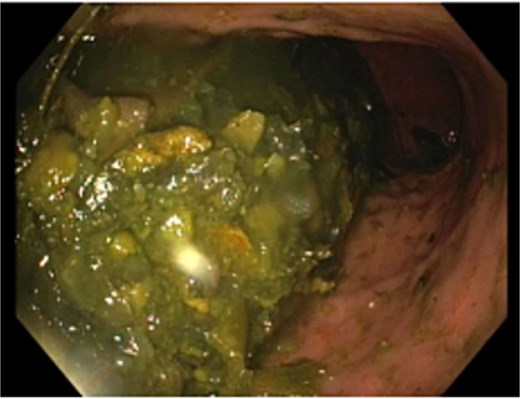

A nasogastric tube was inserted, which drained 2700 ml of green-brown fluid with symptomatic improvement. To assess for alternative causes of duodenal obstruction, upper gastrointestinal endoscopy was performed, which identified a large non-obstructing phytobezoar in the gastric body with associated erosive gastritis (Fig. 2). Upon entering the duodenum, a second phytobezoar causing luminal obstruction was found at the duodenojejunal flexure, which was removed with a Roth net (Fig. 3). Following this, no persistent extrinsic compression of the duodenum was noted endoscopically.

Bezoar material in the gastric body with associated erosive gastritis.